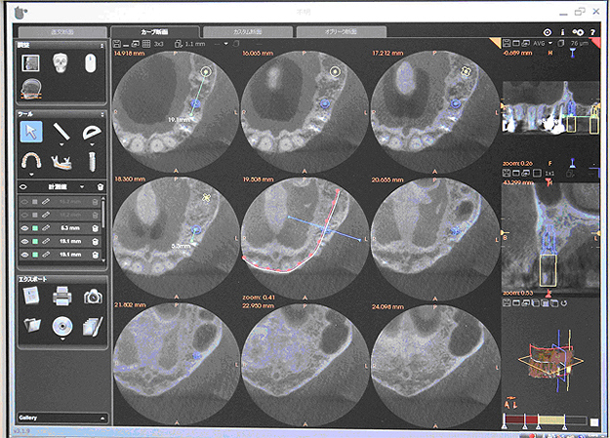

最新のパノラマと3Dセンサーを装備した回転式デジタルレントゲンで、3D機能により立体的な画像で写し出されるため、従来の平面(2次元)の情報よりはるかに多く、正確な情報が得られ、さまざまな歯科診療でより正確で安全な診断が行えます。特に、埋伏知歯の抜歯、過剰歯の抜歯、インプラント手術や歯周病治療、歯の根の病気に関係する治療の正確な診断・治療計画には、3次元歯科用CTによる撮影が威力を発揮します。

親知らずなど埋状歯(顎に埋もれた歯)を抜歯する場合、歯根(歯の根っこ)の位置や神経の位置を確認しておく必要があります。CTによる断層撮影はその位置関係を明確にでき、正確な審査・診断により、治療の安全性を高めます。

いわゆる神経の治療ですが、根の先で神経が複雑に分岐していたり、根の先に病巣があり難治性の症例でも根先の状態を3Dで正確に審査する事で治癒率を向上させる事が出来ます。

歯の周囲の骨の破壊の程度が、立体的に把握でき、歯周病の進行度が正確に診断でき、最善の治療計画をたてることができ、治療の予知性が高くなります。特に臼歯部は根形態が複雑で歯周病による骨の吸収状態を把握する事が出来るので、再生療法を行う場合の診断に非常に役立ちます。

親知らずや位置異常歯、過剰歯を抜く場合でも歯の位置や向き、湾曲の程度また神経との位置関係が3次元的にわかることで、抜歯が手際よく安全に行えます。

インプラントを埋める部位の骨の質や厚み・形態、神経・血管の位置が正確に分かり、3D画面上でのインプラント埋入のシュミレーションソフトによって確実な診断が可能となります。それにより、インプラント治療の安全性が飛躍的に向上します。術中にもCT撮影ができることで、インプラントの位置や方向などの確認ができ、より安全・正確にインプラント手術をすることができます。現在はCT審査なしでのインプラント手術は考えられないと言うのが常識のようです。でも診断するのは人間・・・正しい診断を下さないと良い機械も無駄になってしまいます。